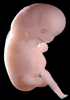

Carnegie Stage 19 (47 post-ovulatory days)

Most embryos at stage 19 are approximately 47-48 post-ovulatory days old and measure 17-20 mm in length. Distinguishing criteria for this stage include straightening of the trunk, the limbs extend nearly directly forward, toe rays are prominent, but interdigital notches have not yet appeared in the foot.

Although some of the photographs below show abnormal embryos, the animations and MRI slice images all depict normal embryos. Abnormal embryos are noted in the titles of the large photos when they are opened.